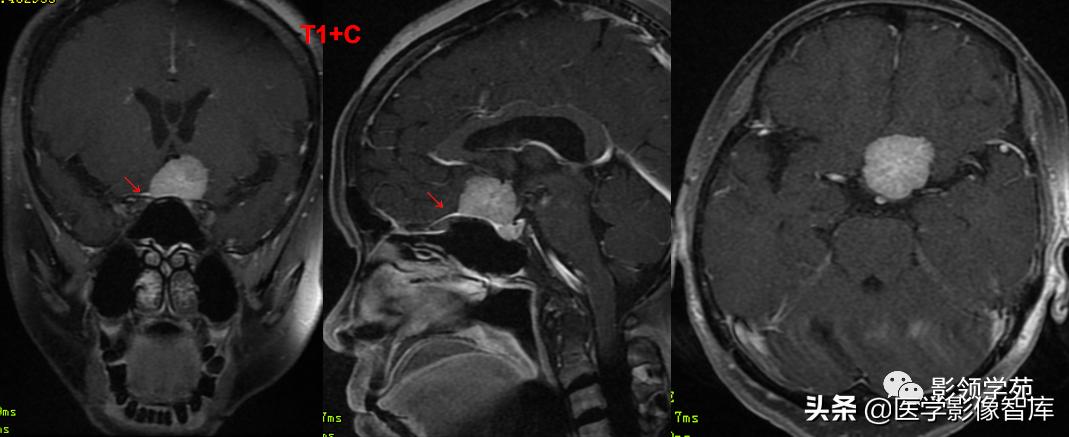

男 62岁,右眼视朦半年

鞍区见一类圆形稍高密度肿块影,密度较均匀,边界较清,位置稍偏右,向上突入鞍上池内,周围骨质未见破坏。

前颅窝底、鞍前区见一肿块影,呈等T1等T2信号,信号均匀,边缘清楚,以宽基底与颅底接触。

病灶呈均匀明显强化(馒头样),见脑膜尾征;肿块后缘部分进入鞍内,挤压垂体前方和视交叉,垂体柄显示不清楚。

右侧大脑前动脉A1段完全被肿瘤包绕;左侧大脑前动脉A1段与肿瘤分界不清,但无明显包绕和推移。双侧海绵窦未见异常征象。